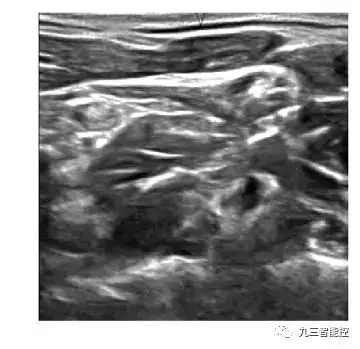

原始图像

(1)乳腺癌细胞